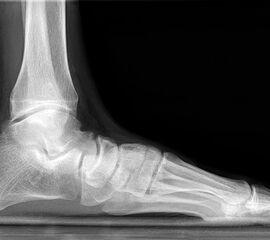

Auf dem linken Bild (a) Varusarthrose des oberen Sprunggelenks mit deutlicher Mehrbelastung der medialen Gelenkanteile. Dort bereits deutlich sichtbarer Knorpelverlust. Rechtes Bild (b) Valgusarthrose des oberen Sprunggelenks. Erhöhte Druckbelastung in de

Abbildung 1

Die Standardröntgendiagnostik bei Fußfehlstellungen und asymmetrischen Arthrosen besteht in stehenden Aufnahmen des Fußes in 2 Ebenen (dorsoplantar und lateral), sowie einer stehenden ap Aufnahme des Sprunggelenks und eine „hindfoot alignment view“ nach Saltzman, mit der die inframalleoläre Rückfußachse beurteilt werden kann 7. Ganzbeinstandaufnahmen sind essentiell, um die mechanische Achse der gesamten unteren Extremität zu analysieren. Zur genauen Analyse des Knorpelzustands bietet sich die Kernspintomographie an. Für spezielle Indikationen steht das SPECT-CT zur Verfügung.